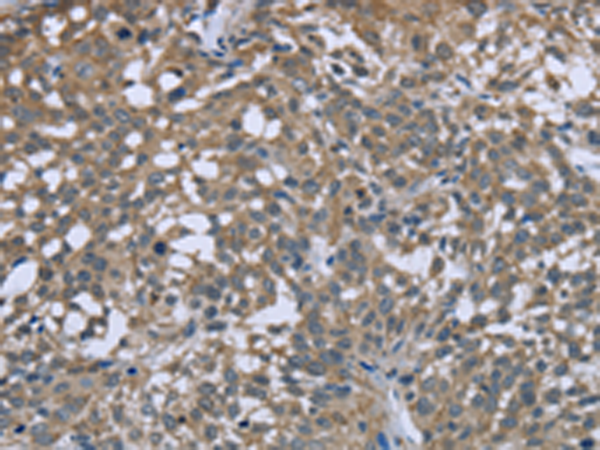

分类: 科研抗体货号: P08314别名: MLSTD1; SDR10E2应用: WB,IHC反应种属: Human, Mouse